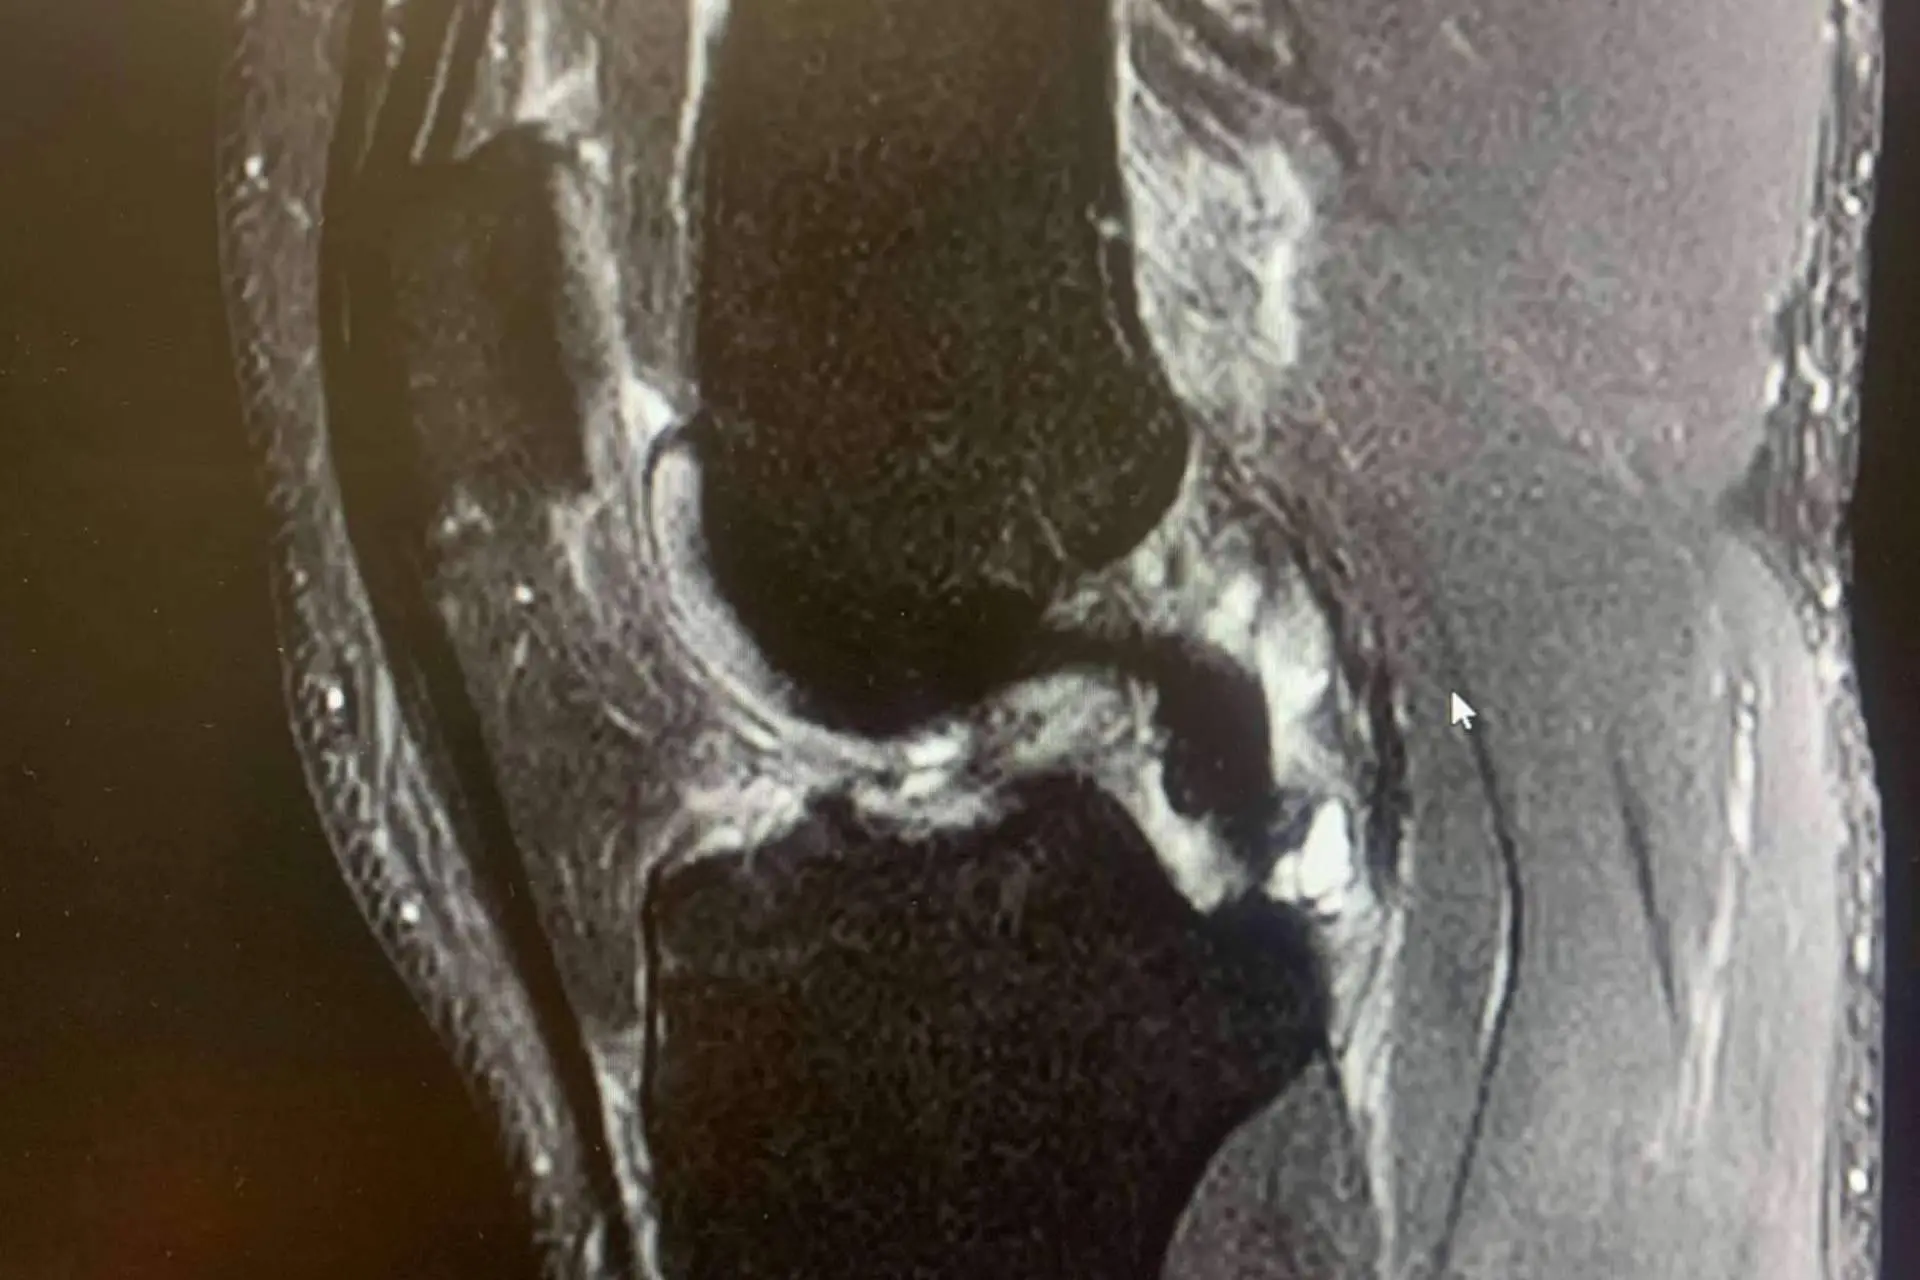

El ligamento cruzado anterior es una banda de tejido fuerte y resistente que se encuentra en la rodilla y juega un papel crucial tanto en la estabilidad como en la capacidad de control de esta articulación.

Las lesiones de LCA suelen ocurrir en situaciones en las que la rodilla está sometida a un estrés repentino y excesivo, sobre todo cuando la pierna está en apoyo y se somete a una torcedura en valgo (“metiendo la rodilla hacia dentro”) o con una torsión de la pierna hacia afuera con torsión interna del muslo, con la rodilla en flexión.